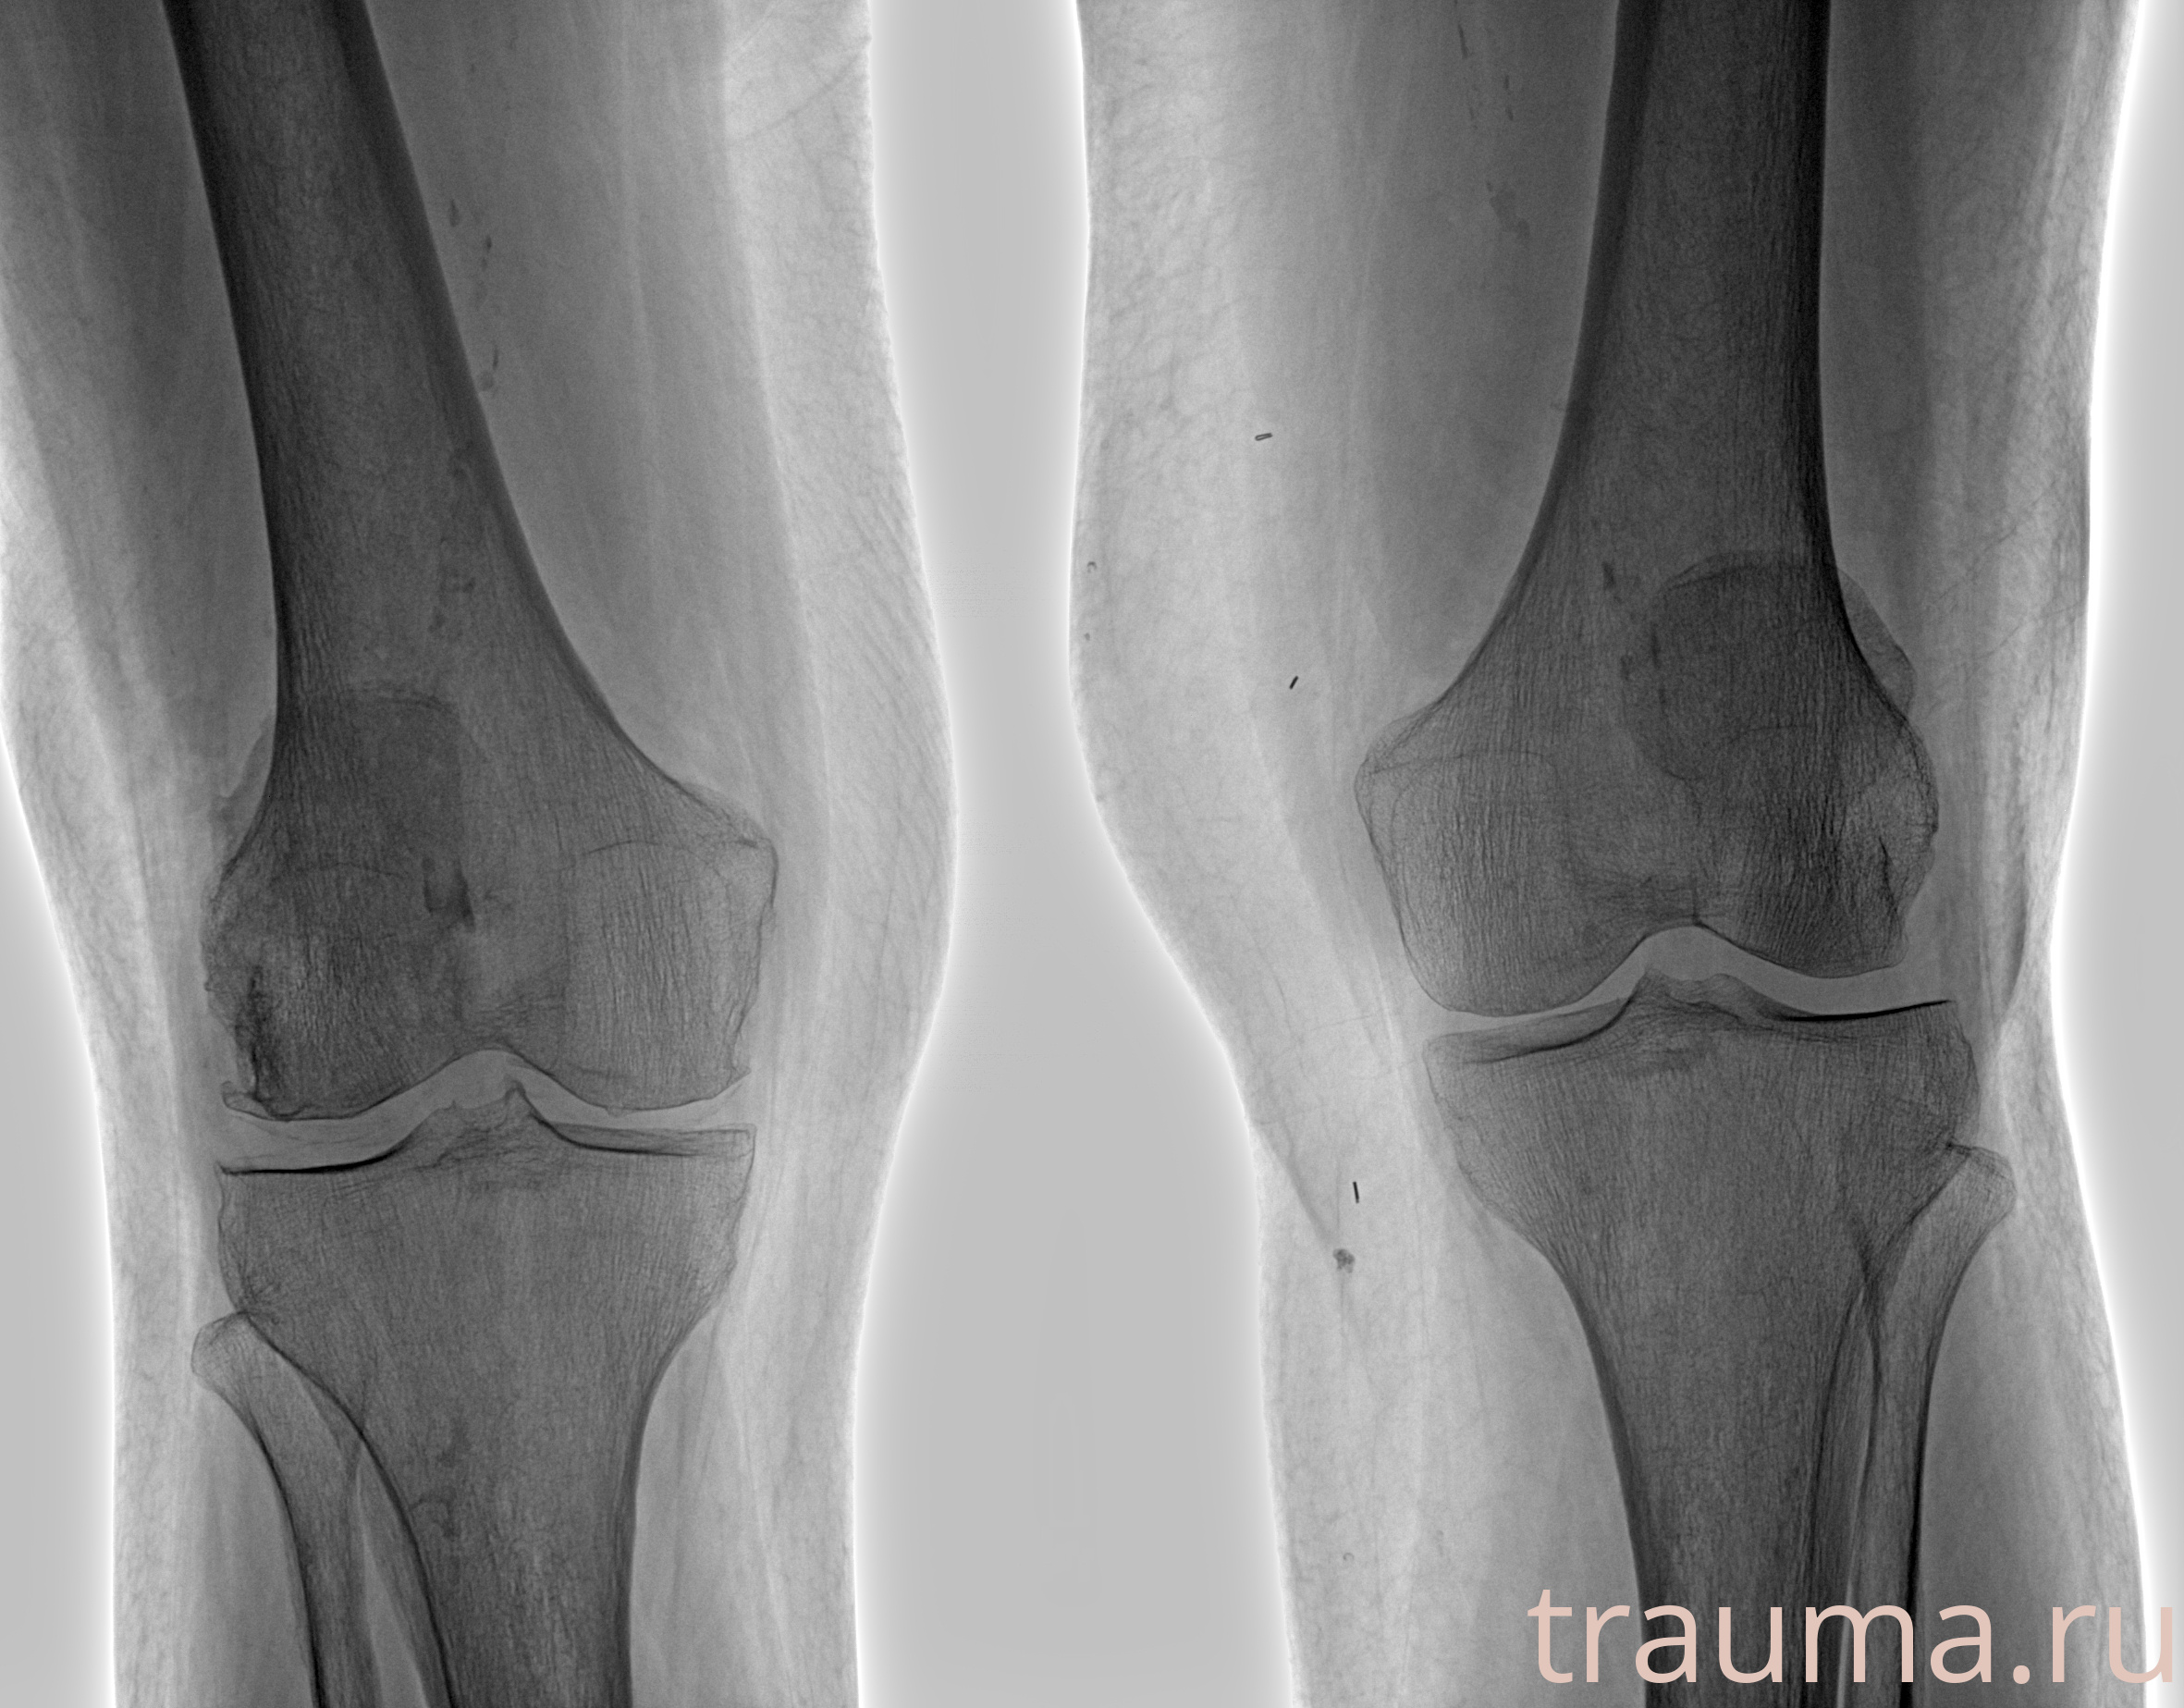

Рентгенограммы

Рентген на дому: по вашему адресу приезжает врач-рентгенолог, травматолог-ортопед с мобильным рентгеновским аппаратом, проводит диагностику травмы или заболевания, делает необходимые рентгенограммы, дает рекомендации по дальнейшему лечению. Получить качественные снимки в домашних условиях возможно благодаря уникальной методике, разработанной МосРентген Центром для института  Склифосовского